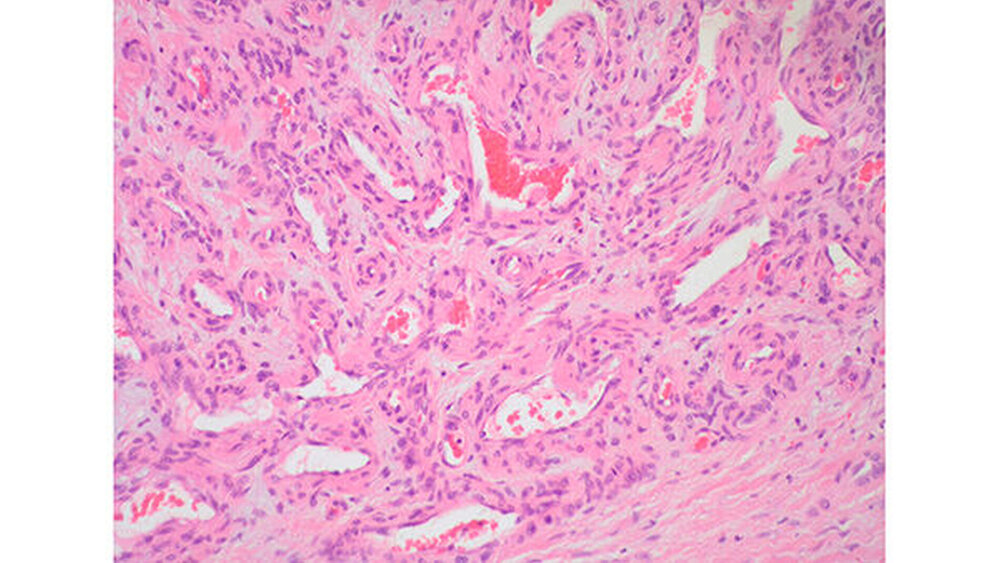

Die Patientin hatte keinerlei Symptomatik, bei bidigitaler Palpation gelang es nicht, die Raumforderung zu tasten. Zur weiteren Abklärung wurde die Raumforderung über einen enoralen Zugang nach Inzision anterior der Karunkula dargestellt (Abbildung 3) und entfernt (Abbildung 4). Die histopathologische Aufarbeitung erbrachte die Diagnose eines Hämangioms (Abbildungen 5 und 6).

Hämangiome gehören zu den benignen vaskulären Tumoren und treten meist in der Haut auf. In der Kopf-Hals-Region findet man sie des Weiteren häufig im Bereich des anterioren Nasenseptums, der Nasenmuscheln und der Nebenhöhlen sowie im Bereich des Larynx und der Speicheldrüsen, wobei die Parotis fast exklusiv betroffen ist [Barnes et al., 2005].

Hämangiome können mit etwa einem Prozent der Fälle intramuskulär zu liegen kommen [Nair et al., 2010]. Intramuskuläre Hämangiome sind relativ selten, jedoch gehören sie unter den tief liegenden Weichteiltumoren wieder zu den häufigeren Entitäten [Fletcher et al., 2002].